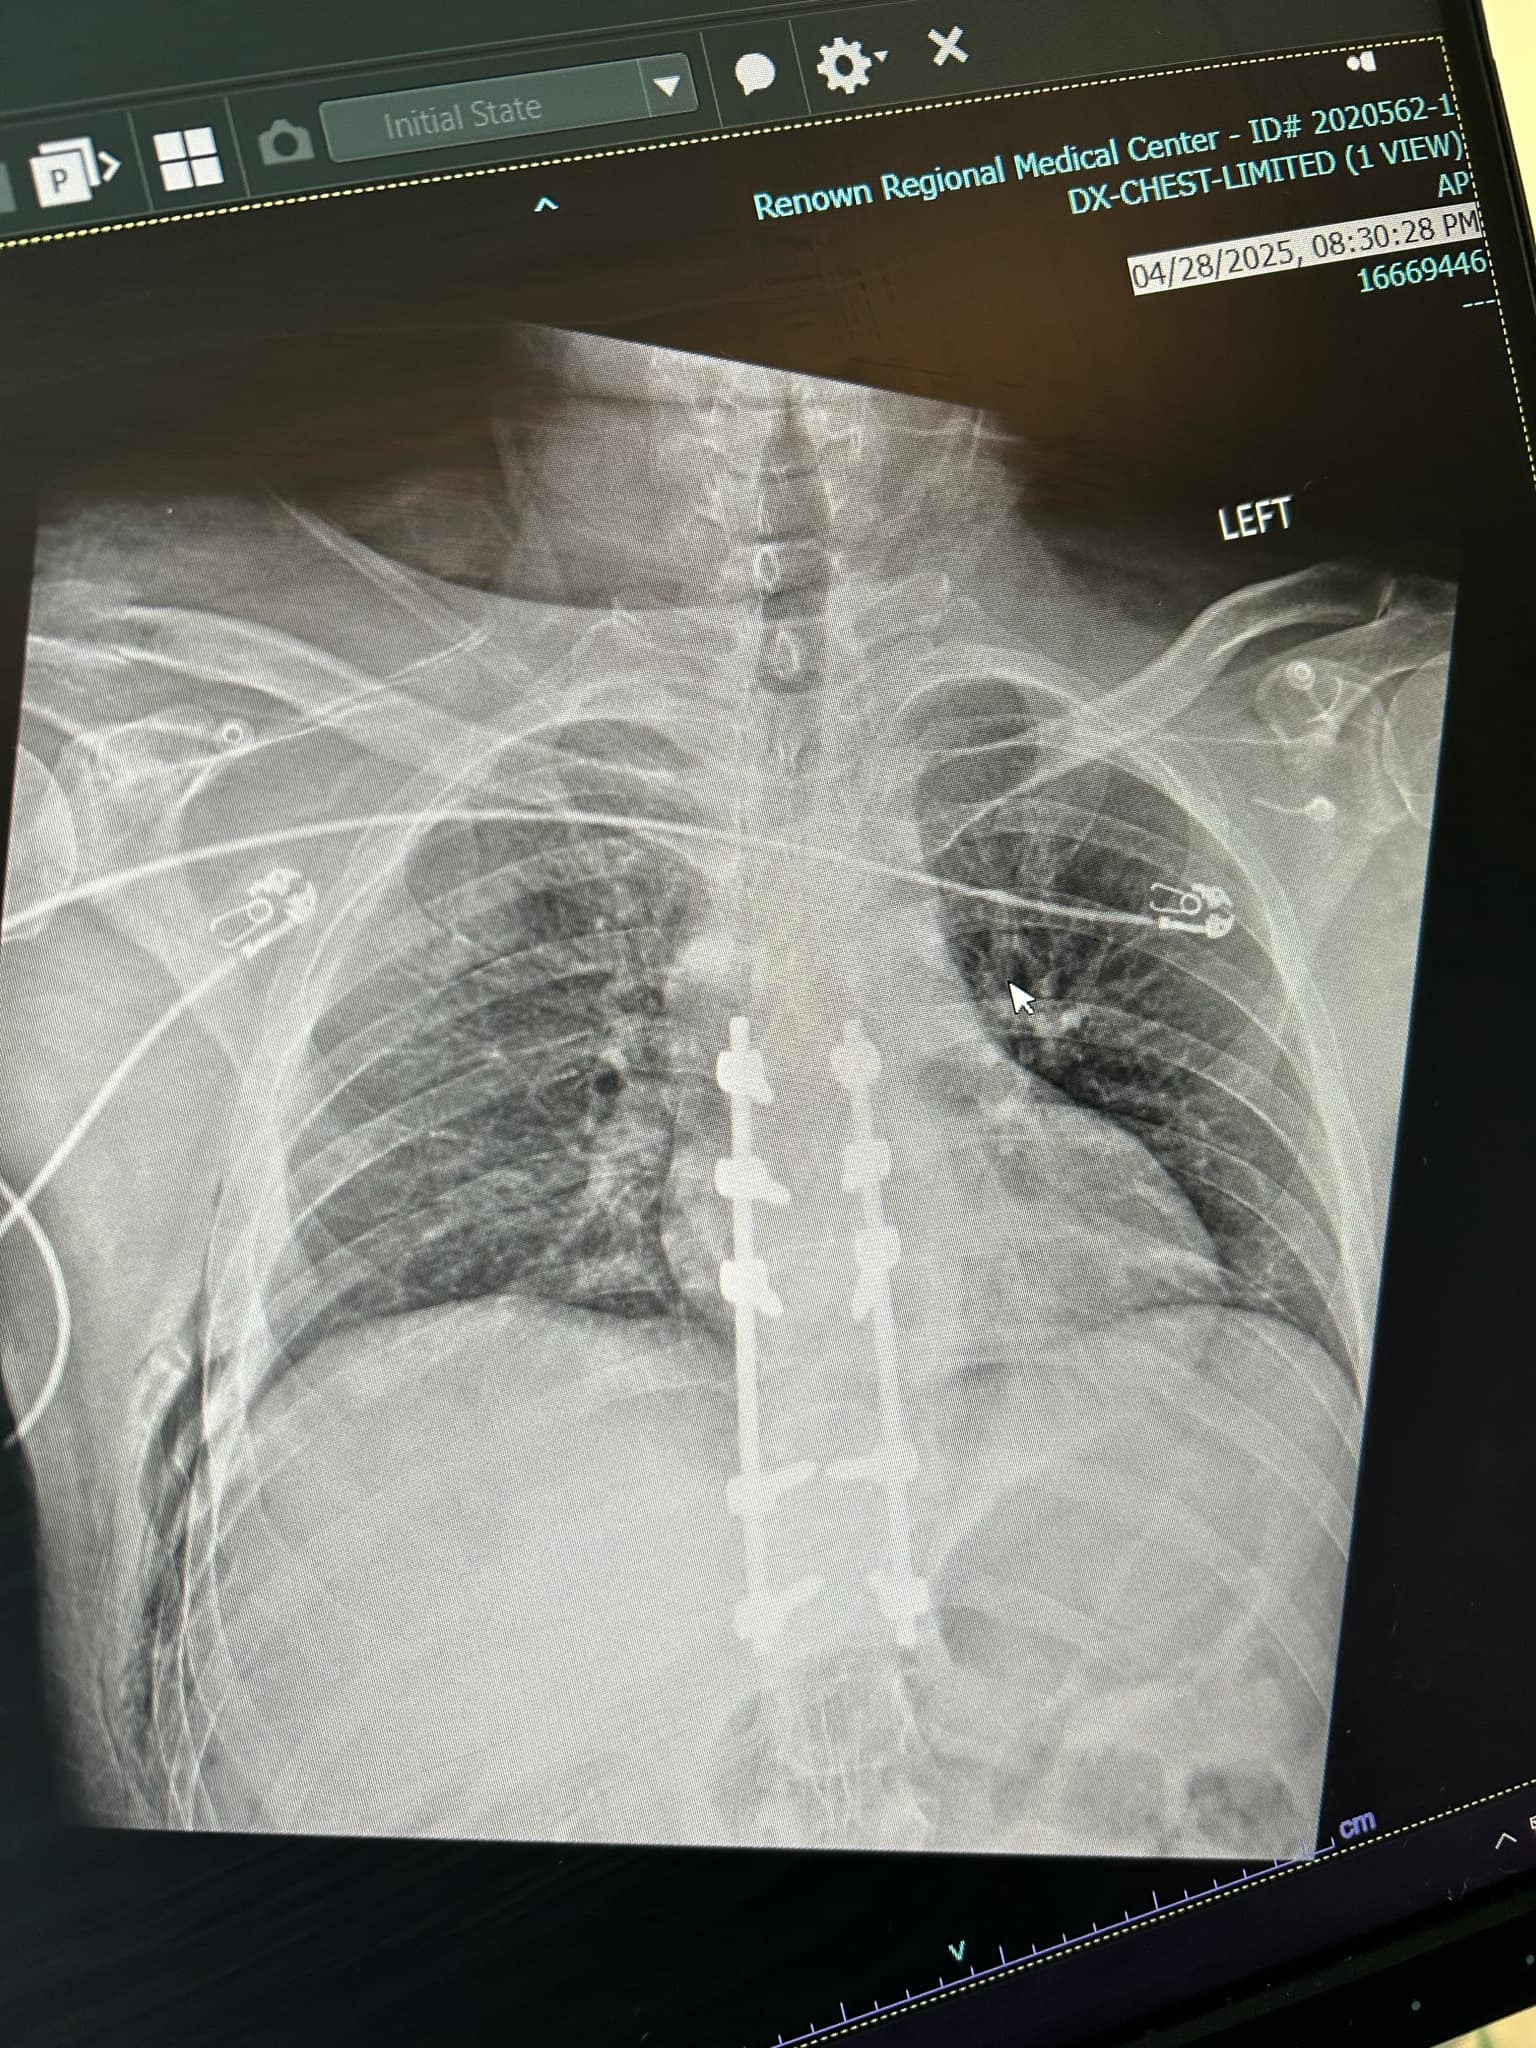

On April 28th, my partner Erick was in a serious mountain biking accident. He suffered a burst fracture in his spine (T1), a shoulder broken in three places, and eight fractured ribs. He’s already undergone emergency spinal surgery (a four-level fusion), and the recovery ahead will be long and intense—expected to take at four to six months, with physical therapy, follow-up scans, and a lot of healing time at home.